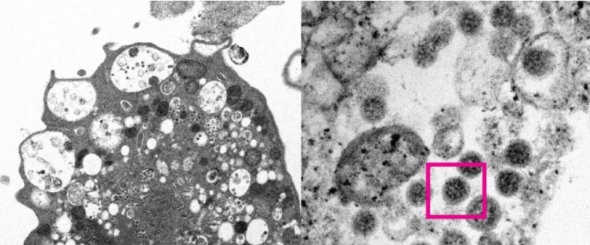

Университет Гонконга опубликовал первое изображение штамма коронавируса Omicron, сделанное с помощью электронного микроскопа.

Снимок 8 декабря обнародовали на сайте университета.

"На первом снимке (слева) показана клетка Vero E6 почки обезьяны после заражения новым Сovid-штаммом. Он демонстрирует повреждение клетки с набухшими везикулами, которые содержат маленькие черные вирусные частицы", - говорится в сообщении.

На втором снимке (справа) - увеличенная инфицированная клетка Vero E6. На нем видно скопление вирусных частиц с шипами в форме короны.